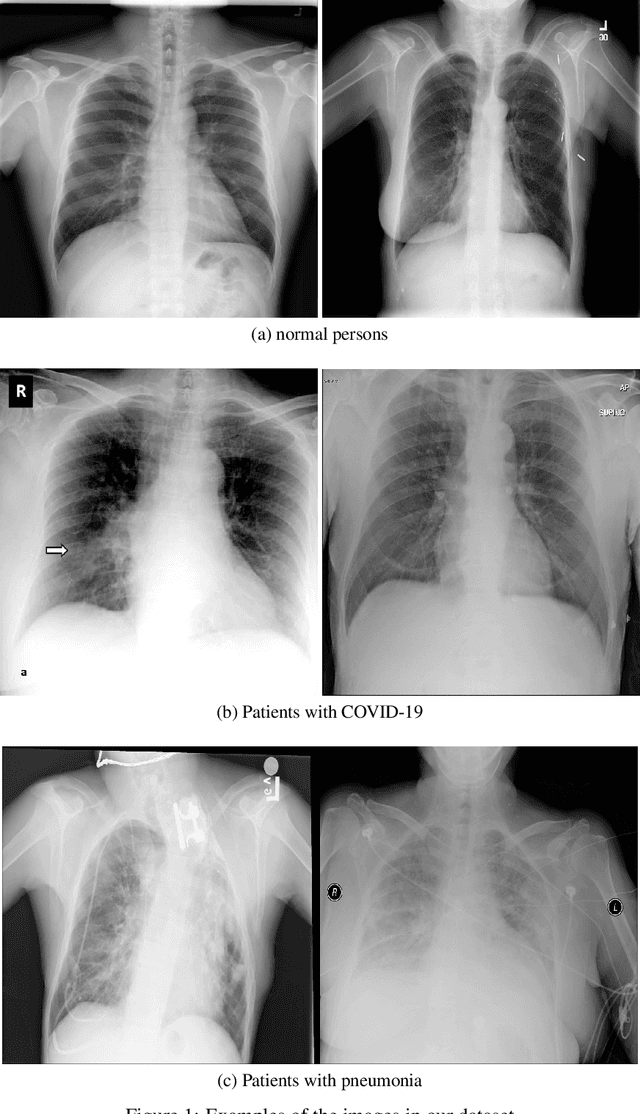

Abstract:COVID-19 has become a serious health problem all around the world. It is confirmed that this virus has taken over 126,607 lives until today. Since the beginning of its spreading, many Artificial Intelligence researchers developed systems and methods for predicting the virus's behavior or detecting the infection. One of the possible ways of determining the patient infection to COVID-19 is through analyzing the chest X-ray images. As there are a large number of patients in hospitals, it would be time-consuming and difficult to examine lots of X-ray images, so it can be very useful to develop an AI network that does this job automatically. In this paper, we have trained several deep convolutional networks with the introduced training techniques for classifying X-ray images into three classes: normal, pneumonia, and COVID-19, based on two open-source datasets. Unfortunately, most of the previous works on this subject have not shared their dataset, and we had to deal with few data on covid19 cases. Our data contains 180 X-ray images that belong to persons infected to COVID-19, so we tried to apply methods to achieve the best possible results. In this research, we introduce some training techniques that help the network learn better when we have few cases of COVID-19, and also we propose a neural network that is a concatenation of Xception and ResNet50V2 networks. This network achieved the best accuracy by utilizing multiple features extracted by two robust networks. In this paper, despite some other researches, we have tested our network on 11302 images to report the actual accuracy our network can achieve in real circumstances. The average accuracy of the proposed network for detecting COVID-19 cases is 99.56%, and the overall average accuracy for all classes is 91.4%.